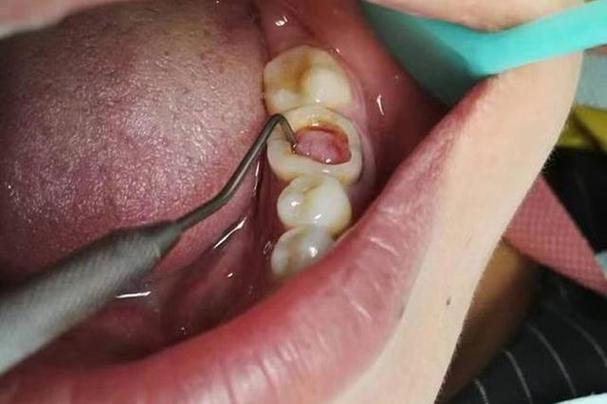

(图片来源网络,侵删)- 材料: 玻璃离子水门汀(传统型或树脂改良型)。